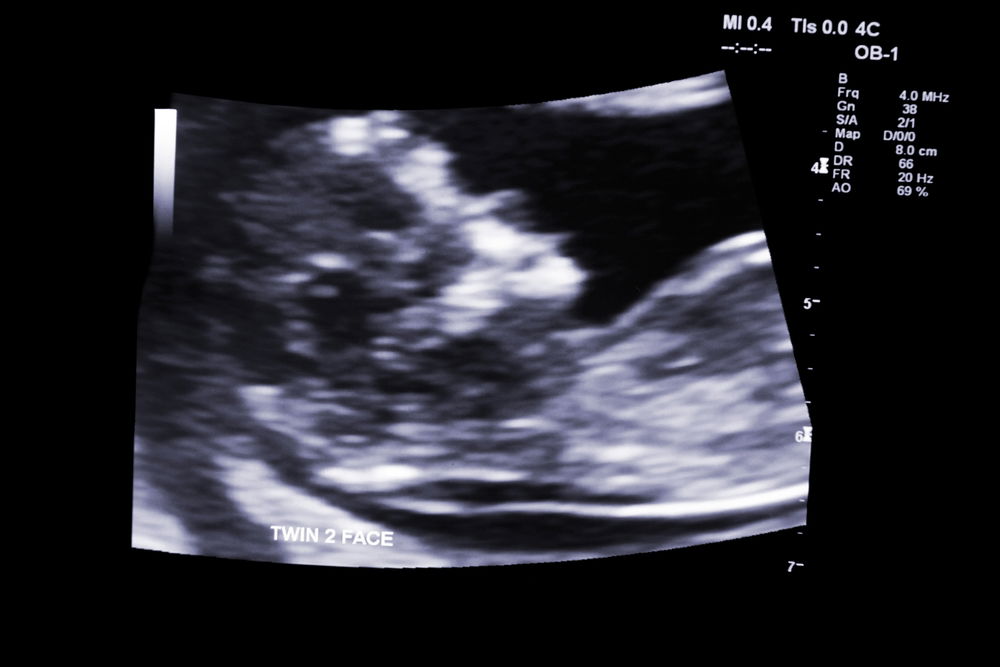

לפי דיווחים בתקשורת המצרים, הרופא ערך לה בדיקת אולטרסאונד ולאחר מכן נדהם ובישר לה כי היא בהיריון של תשעה עוברים בו זמנית.

מדובר במקרה נדיר מאוד, מהבודדים כדוגמתו שתועדו אי פעם בהיסטוריה הרפואית המודרנית.